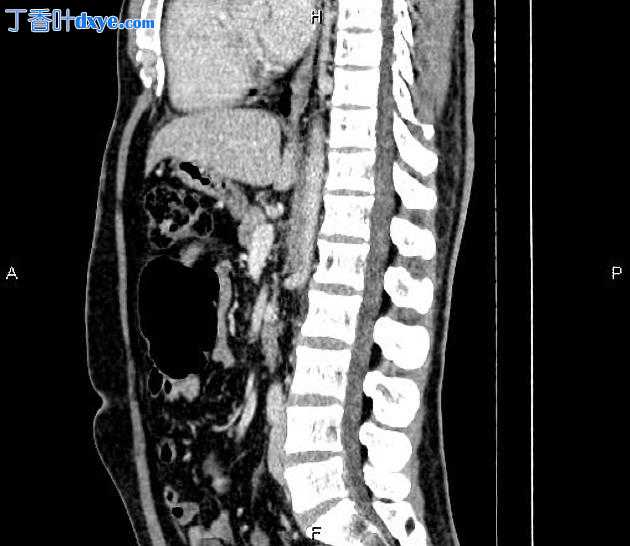

Coronal C+ portal venous phase

6.jpeg

在右肝叶小于 55 mm 处可见三个相邻的厚壁囊性病变。

此外,还描绘了一个直径为 15 毫米的低密度肝病灶,位于第 4 肝段(Couinaud 的命名法),显示早期外周、结节状强化和向心性充盈。特征与血管瘤最相容。